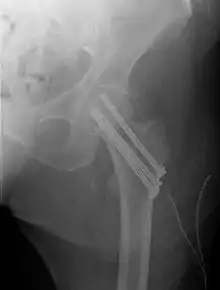

Intracapsular fractures

Fracture treated with cannulated screws

For low-grade fractures (Garden types 1 and 2), standard treatment is fixation of the fracture in situ with screws or a sliding screw/plate device. This treatment can also be offered for displaced fractures after the fracture has been reduced.

Fractures managed by closed reduction can possibly be treated by percutaneously inserted screws.[37]

In elderly patients with displaced or intracapsular fractures surgeons may decide to perform a hemiarthroplasty, replacing the broken part of the bone with a metal implant.[38] However, in elderly people who are medically well and still active, a total hip replacement may be indicated. Independently mobile older adults with hip fractures may benefit from a total hip replacement instead of hemiarthroplasty.[39]

Traction is contraindicated in femoral neck fractures due to it affecting blood flow to the head of the femur.[40]

The latest evidence suggests that there may be little or no difference between screws and fixed angle plates as internal fixation implants for intracapsular hip fractures in older adults.[41] The findings are based on low quality evidence that can't firmly conclude major difference in hip function, quality of life, and additional surgery.